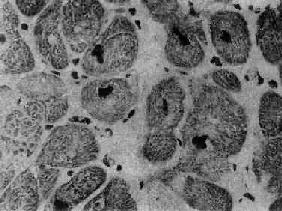

图8-35 肥厚性心肌病 心室横断面(上面观),左心室腔缩小,心室壁均匀增厚,整个心肌布满白色纤维化区,室间隔与后壁厚度之比仅稍大于正常值(1.4) 镜下,心肌细胞显著肥大,核大而浓染(图8-36),核周有亮区包围,组织化学染色证明为糖原堆积,具有一定的诊断意义。心肌细胞排列紊乱较其它型心肌病为甚,而且常呈旋涡状或缠绕呈簇状排列(图8-37),细胞内肌原纤维不呈平行排列,而是向各个方向、互相交错排列。常有间质纤维化灶形成,但以内膜纤维化,尤其位于主动脉瓣下区的内膜纤维化为突出。位于肥厚的室间隔内的冠状动脉分支管壁常有增厚现象。

图8-36 肥厚性心肌病 心肌细胞肥大,核大浓染 (采自Edwards)